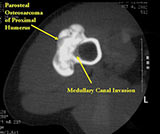

- Parosteal osteosarcomas that are present for prolonged periods of time may either have areas that become higher grade or dedifferentiate. Dedifferentiation refers to a portion of the tumor changing and becoming a high grade type of sarcoma. In addition, parosteal osteosarcomas that are present for a prolonged period of time can invade the bone (medullary canal) that it arose from. Tumors that have undergone dedifferentiation or invaded the underlying bone are more aggressive and have a higher risk of metastasizing (spreading). This is important to know for treatment purposes. Typically, low grade parosteal osteosarcomas are treated with surgery alone. Parosteal osteosarcomas with high grade areas may also be treated with chemotherapy in addition to surgery.

- There may be invasion of the medullary canal with long standing disease

MRI/CT:

- Useful for determining medullary invasion

- Can help discern areas that may be high grade

- If it has grown through the cortex, there may be an intramedullary component

- Metastases more common with medullary invasion, high grade components (grade 3) and dedifferentiation (grade 3 tumors)

- Many parosteal osteosarcomas with intramedullary extension are higher grade lesions or dedifferentiated tumors